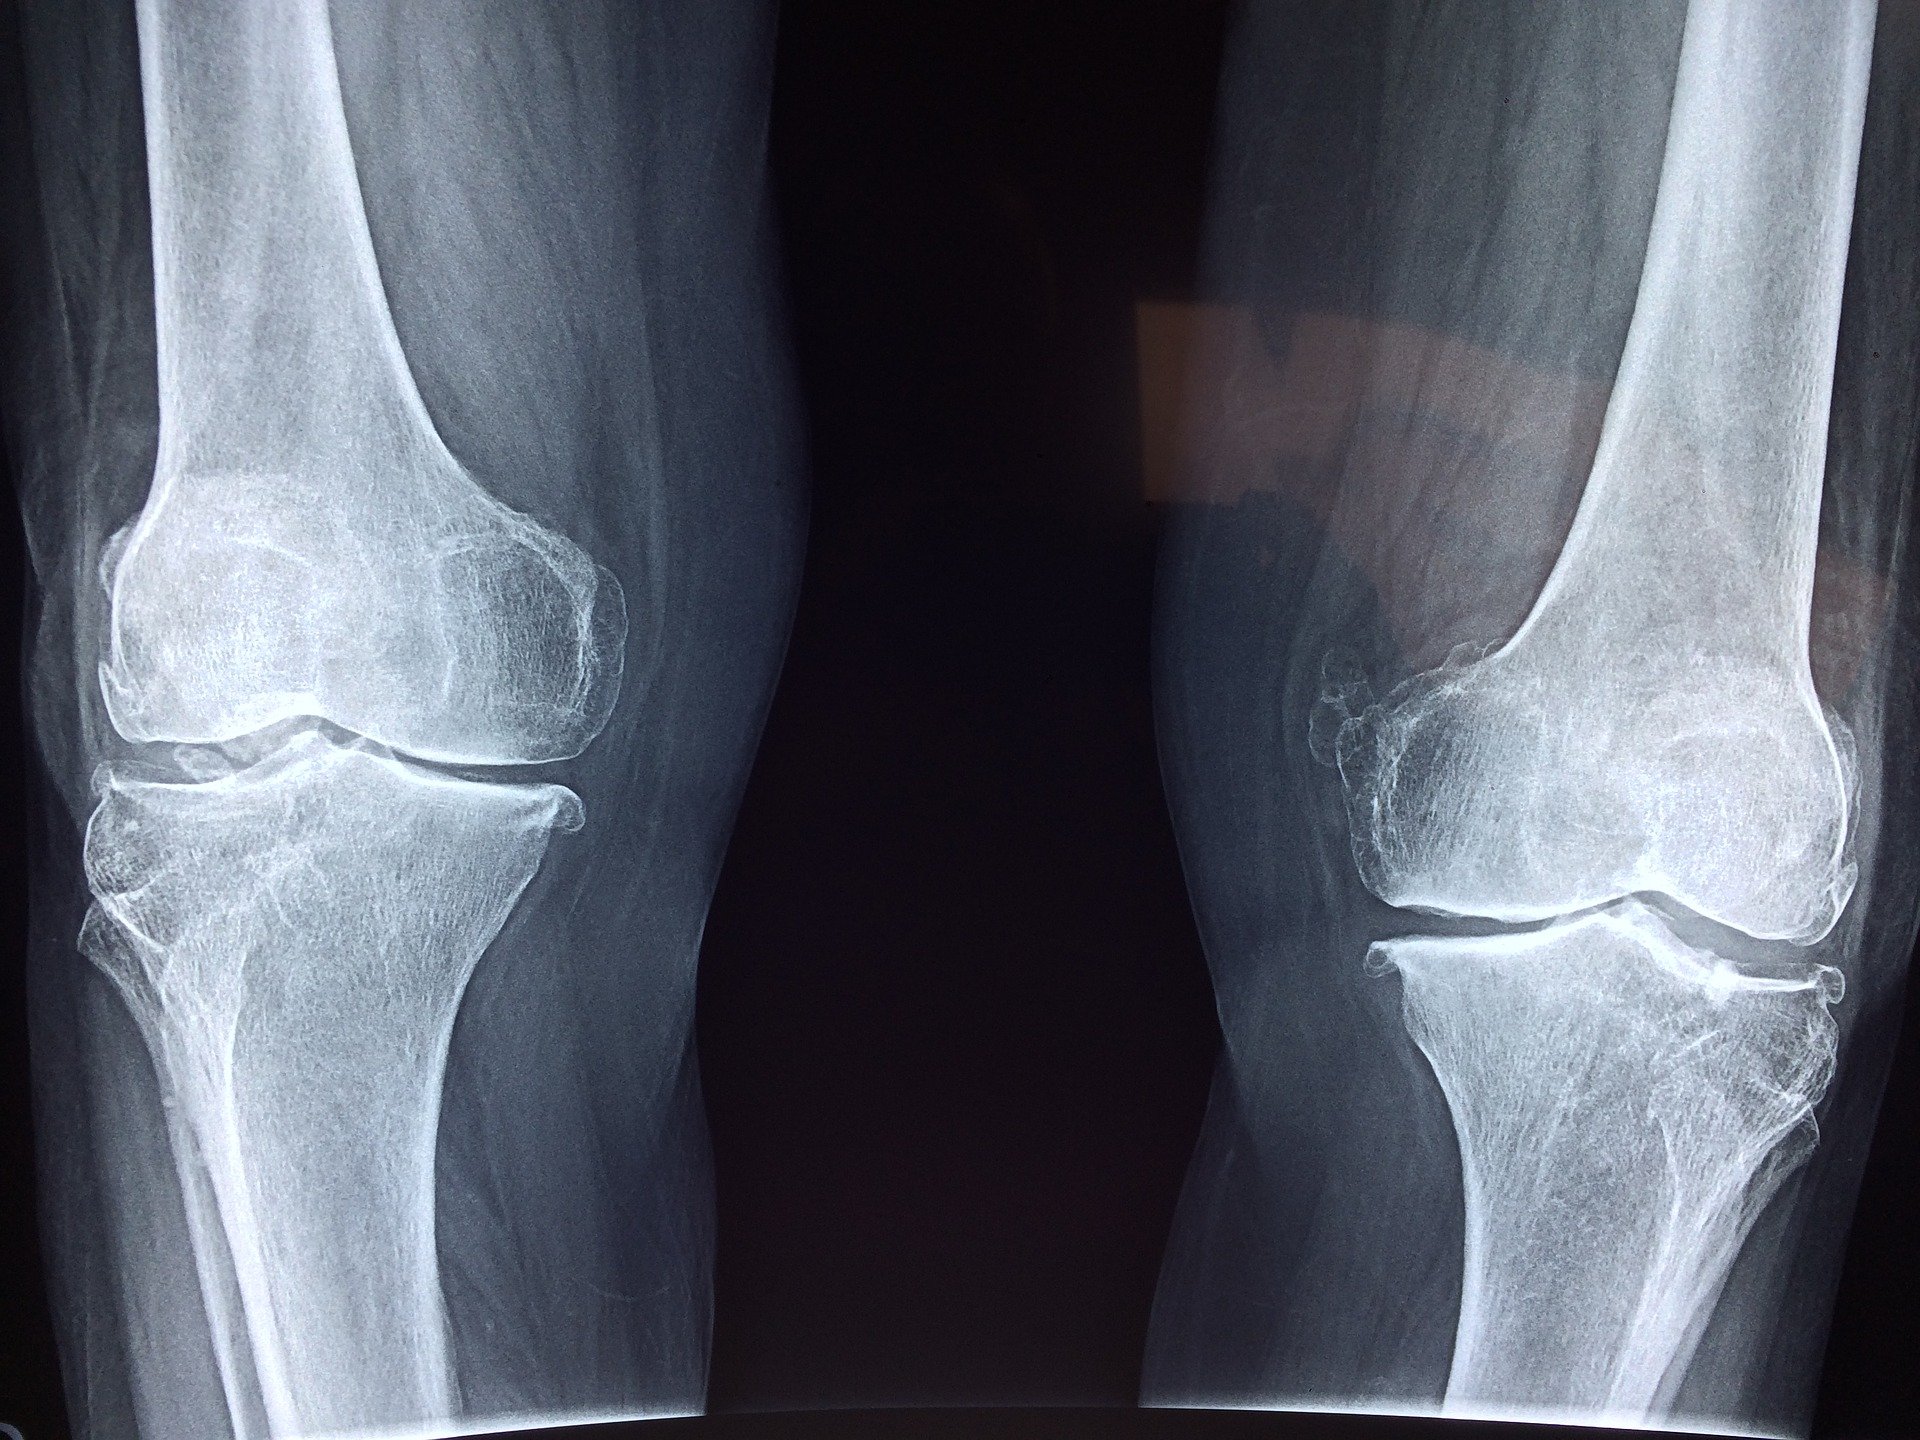

Dobrze znany fakt: Ból i opuchlizna kolan mogą wskazywać na poważny problem zdrowotny. Ważne jest, by skonsultować się z lekarzem, jeśli objawy się nasilą. Zanim udasz się do lekarza, możesz zmniejszyć objawy, stosując domowe sposoby. Zebraliśmy listę najlepszych domowych sposobów na obrzęk, ból i wodę w kolanie. Najlepszym rozwiązaniem jest jednak wizyta u lekarza.